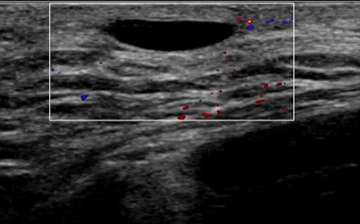

Well-circumscribed, anechoic, parallel, and avascular tubular structure with well-defined borders

The ultrasound above demonstrates a well-circumscribed, anechoic, parallel, and avascular tubular structure with well-defined borders, consistent with a dilated duct. The opposite breast also revealed similar dilation of the ducts, this symmetry is reassuring and benign. Features of ductal dilation which are concerning (and may warrant biopsy) include unilateral breast ductal dilation or a focal ductal dilation in a breast with otherwise normal sized ducts. Furthermore, a dilated duct which is not anechoic (fluid filled or with internal soft tissue nodularity), with an irregular shape, or with indistinct margins are also more suspicious.

Using Doppler ultrasound, the amount of blood flow to an area of interest can be assessed and compared to surrounding tissue. Increased vascularity may suggest inflammation (i.e. infection such as mastitis) or malignancy. Doppler is especially helpful when evaluating for blood flow to cystic lesions, which may suggest a solid component (vascular) rather than debris within a cyst (avascular). In Figure 4, the anechoic structure was avascular on Doppler, consistent with a cystic structure (dilated duct).